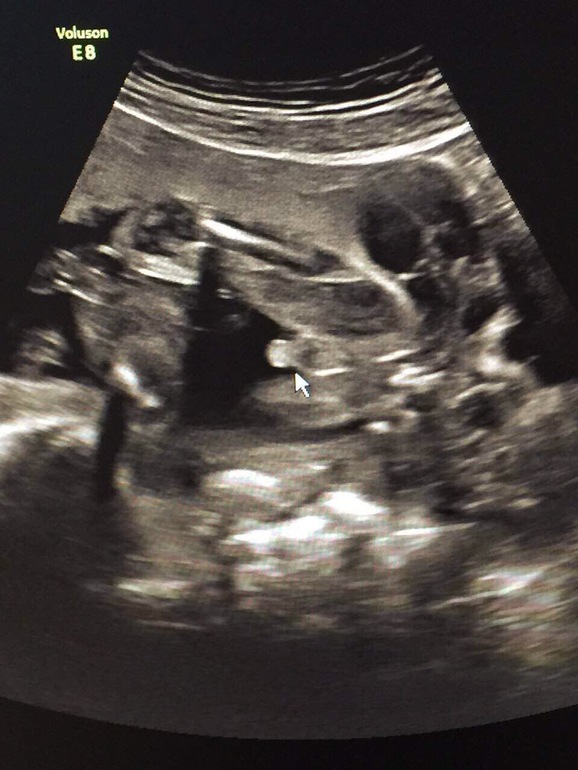

Вот фото моего мальчика, ваш тоже на мальчика похож